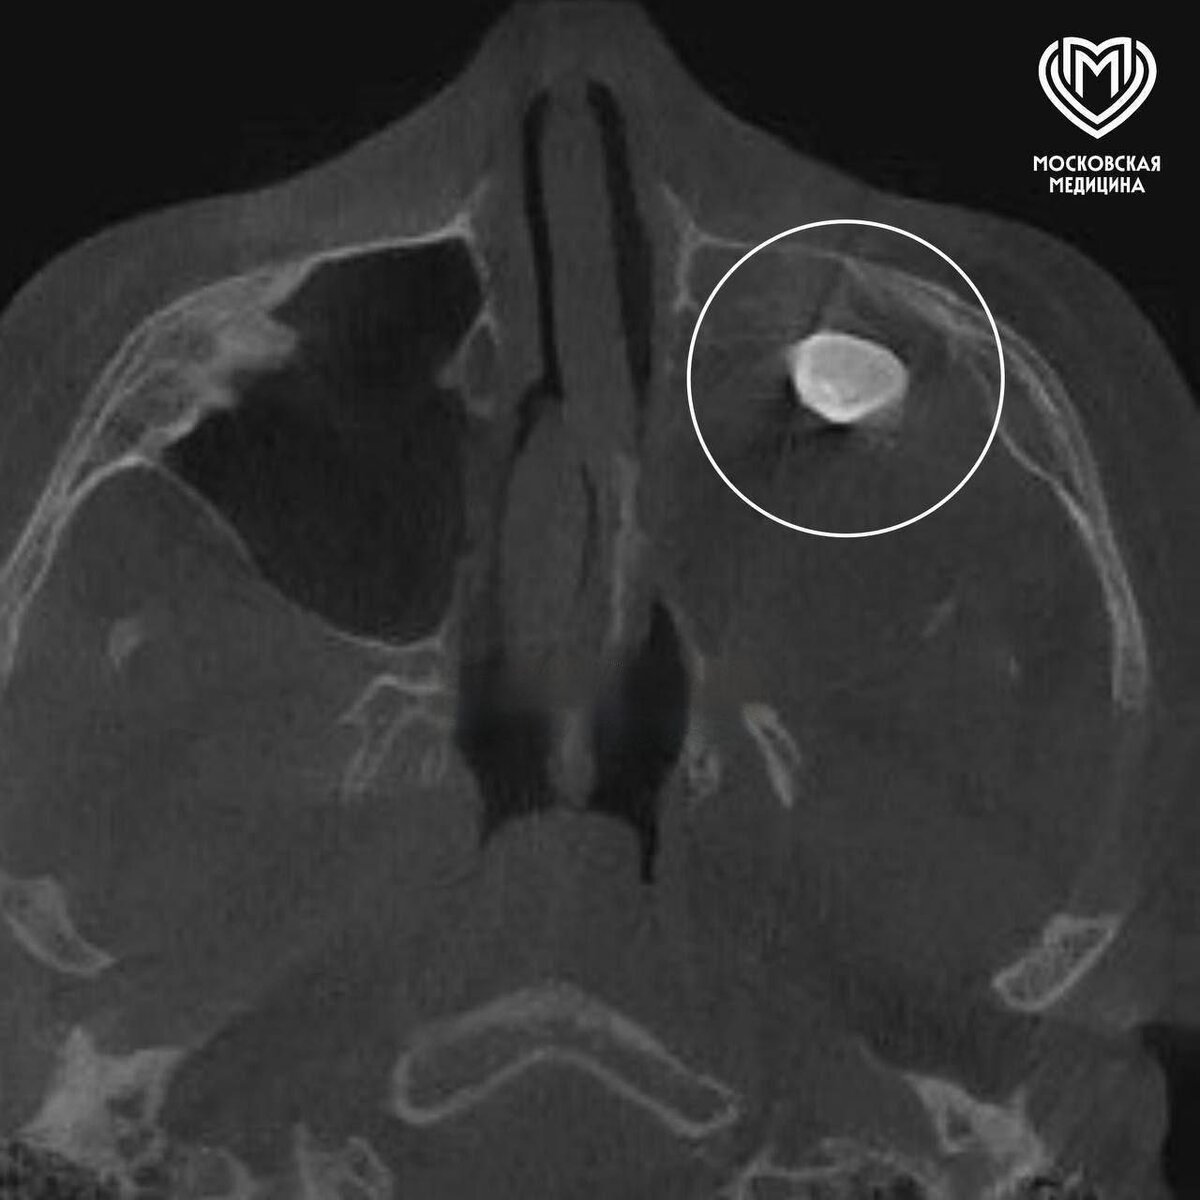

Человеческое тело — удивительная система, где иногда случаются настоящие биологические курьезы. В Москве 15-летний подросток пришел к врачам с жалобами на заложенность носа и асимметрию лица. Каково же было удивление медиков, когда КТ показало... полноценный зуб в гайморовой пазухе!

🔬 Это явление называется "эктопией" — когда орган развивается не на своем месте. В данном случае зачаток зуба мигрировал в верхнечелюстную пазуху. После аккуратного удаления аномалии все симптомы исчезли.